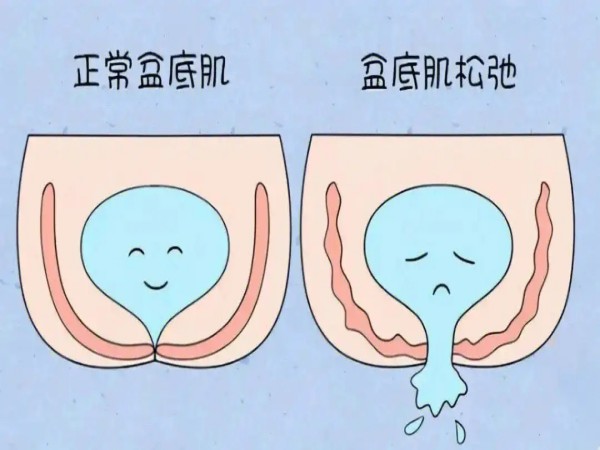

盆腔粘连

如果是由子宫内膜异位症、盆腔炎等疾病引起的继发性痛经,长期不加以治疗,病情持续发展,是可能导致盆腔粘连的。子宫内膜异位症会使子宫内膜组织出现在子宫体以外的部位,这些异位的内膜组织在盆腔内周期性出血、增生,引发周围组织的炎症反应和纤维化,进而导致盆腔粘连。

输卵管堵塞

由子宫内膜异位症、盆腔慢性炎症等疾病导致的继发性痛经,可能引起输卵管阻塞。子宫内膜异位症可使异位的内膜组织在盆腔内生长、出血,形成粘连和瘢痕组织,累及输卵管时,会导致输卵管扭曲、粘连,管腔狭窄甚至阻塞。

不孕

病理性痛经如果得不到及时治疗,可能会影响卵巢功能、输卵管通畅性甚至胚胎着床,从而导致不孕。例如,子宫内膜异位症的患者,异位的子宫内膜组织会影响卵巢功能,导致排卵障碍;盆腔炎则可能导致输卵管粘连,影响精子与卵子的结合;子宫肌瘤也会影响子宫内膜的生长,不利于胚胎着床。

痛经是指女性在月经期间出现下腹疼痛,并伴有腰酸、恶心、呕吐等症状。痛经的发生原因多种多样,包括生理性痛经和病理性痛经。生理性痛经通常是由于子宫内膜前列腺素含量过高,导致子宫过度收缩引起;而病理性痛经则多是由于盆腔器质性疾病导致,比如子宫内膜异位症、盆腔炎、子宫肌瘤等。